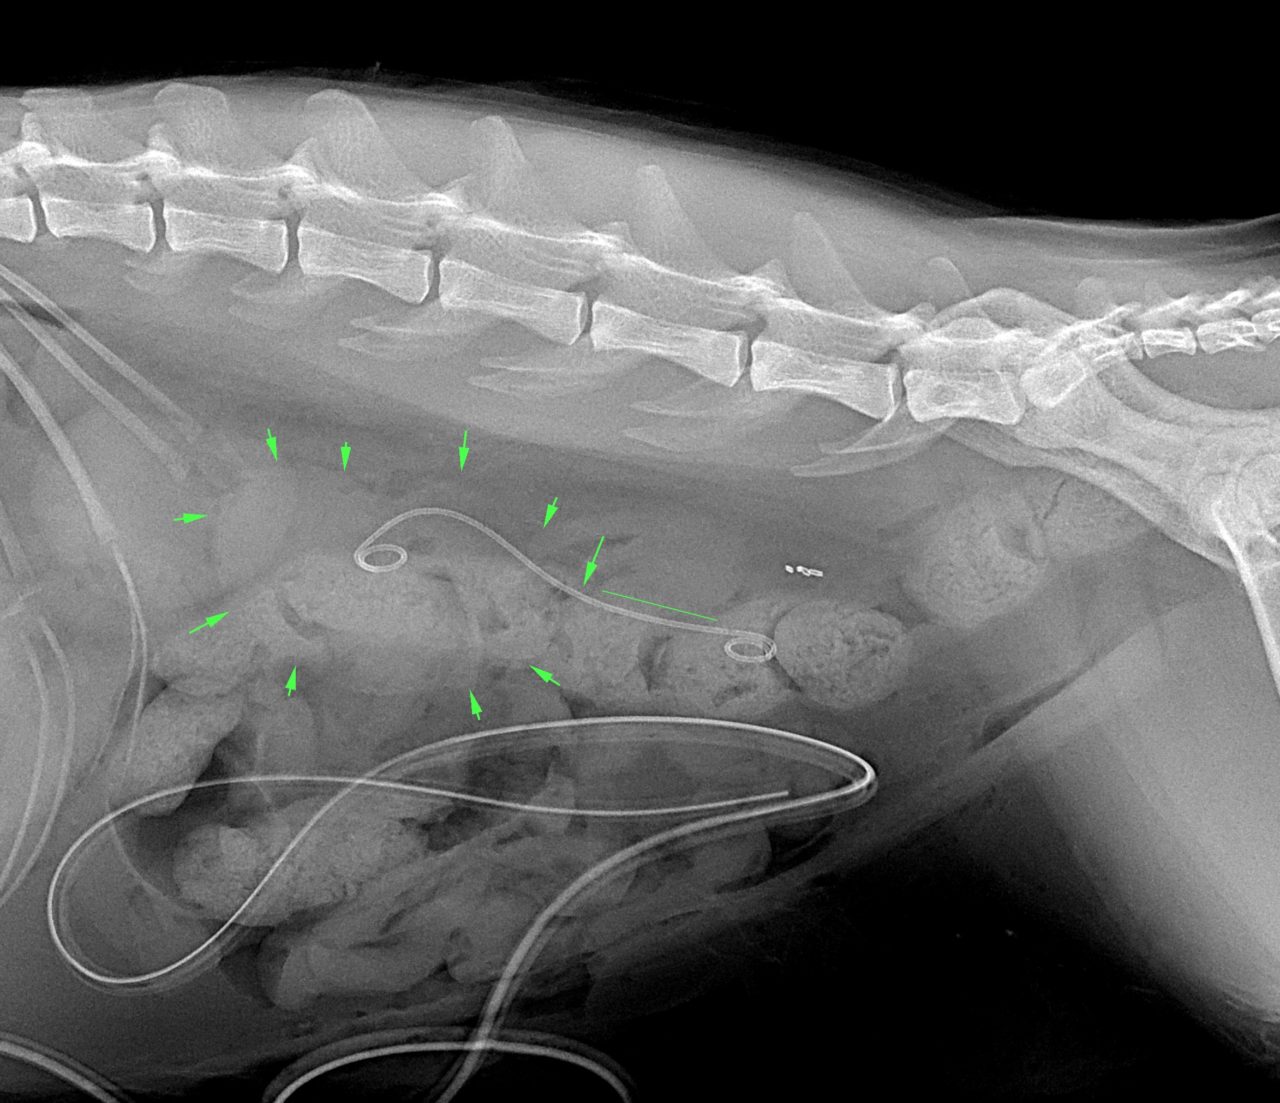

たった1mmの大きさの尿管結石でも猫の尿管を閉塞してしまうことがあります。血液検査、尿検査、超音波検査、無麻酔CT検査などで外科的に対応すべきか?詳しく評価します。閉塞してもすぐには腎盂の拡張はそれほど顕著ではありませんし、片側のみであれば血液検査に異常値が検出されないこともしばしばです。マイクロサージェリーで短尺ステントと尿管新吻合術で対応しました。通常はシュウ酸カルシウムであり溶解できないので非常に厄介です。